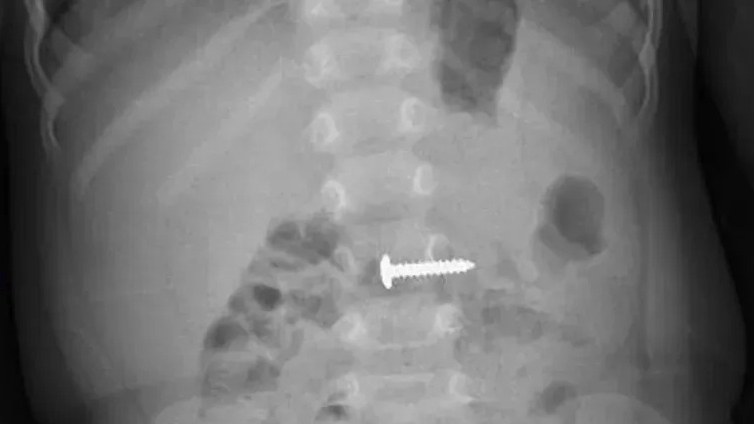

| Que xiên thịt đâm vào vùng thắt lưng, vào thẳng tuỷ sống của bệnh nhân. |

Bệnh nhân được chuyển đến Bệnh viện Việt Đức ngày 6/7/2019 với vết thường thắt lưng trái rất nặng do dị vật cắm vào tủy sống.

Bệnh nhân vào viện trong tình trạng tê bì tầng sinh môn, bí đái và có vết thương ở thắt lưng bên trái.

Tai nạn xảy ra khi nam bệnh nhân đi ăn cưới, có mâu thuẫn với bạn, bạn liền dùng que xiên thịt đâm thẳng vào vùng thắt lưng bên trái.

TS Long cho biết, đây là vết thương ít gặp ở ống sống, bởi lực tác động vào tương đối đặc biệt, cắm thẳng vào tủy sống. Nếu không điều trị kịp thời có thể khiến người bệnh gặp phải những di chứng rất nặng nề. Đặt biệt, các vật tù như xiên thịt khi đâm vào cơ thể có nguy cơ nhiễm trùng cao do dị vật có kèm theo nhiều vi khuẩn, uốn ván... Bởi vậy khi gặp trường hợp tương tự, bệnh nhân cần đến ngay các cơ sở y tế chuyên khoa uy tín để được cấp cứu kịp thời, tránh gây nguy hiểm đến tính mạng.

Với trường hợp này, các bác sĩ đã tiến hành phẫu thuật làm sạch đường vào và lấy hoàn toàn dị vật cho bệnh nhân.